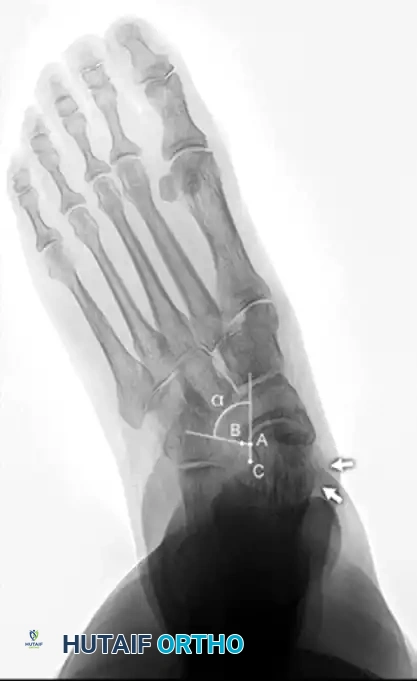

Standard evaluation requires standing AP, lateral, and mortise views of the foot and ankle.

- AP View: Assess the talonavicular coverage angle. Uncovering of the talar head indicates forefoot abduction. The talus-first metatarsal angle (normally 0 degrees) will be elevated.

- Lateral View: Assess the medial longitudinal arch.

- Meary's Angle: The intersection of the longitudinal axis of the talus and the first metatarsal. An angle >4 degrees indicates arch collapse.

- Calcaneal Pitch: Decreased in flatfoot deformity.

- Lateral Tibial-Calcaneal Angle: Arangio et al. demonstrated this angle is a sensitive method for quantifying Achilles tendon contracture in adult-acquired flatfoot.

Measurement of the standing lateral tibial-calcaneal angle, utilized to quantify Achilles contracture.

Preoperative and postoperative radiographic comparisons demonstrating correction of Meary's angle and talonavicular coverage following structural reconstruction.